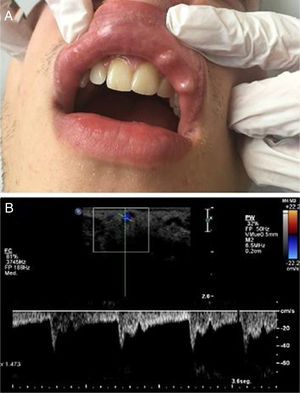

A 25-year-old male with a nibbling habit had been aware of a slowly enlarging reddish-blue, translucent, and pulsatile nodule of the right side of his lower lip of 7 mm. He also refers history of recurrent microulcerations in lower lips for years. Color Doppler and spectral curve confirmed the suspicion of CPLA (Fig. 2).

Figure 2.

(a), Clinical photograph showing an enlarging reddish-blue, translucent, and pulsatile nodule of the right side of the lower lip of 7 mm. (b), Simultaneous spectral and color analysis using Doppler ultrasound show a high resistance forward flow in a large-diameter inferior labial artery branch at the lower lip.